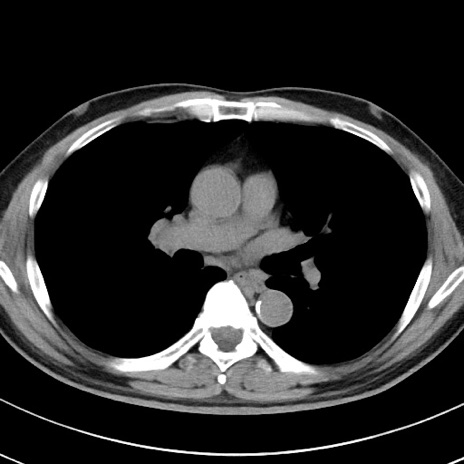

【腹部TIPS】症例29 参考症例 CT(横断像)

症例

70歳代男性